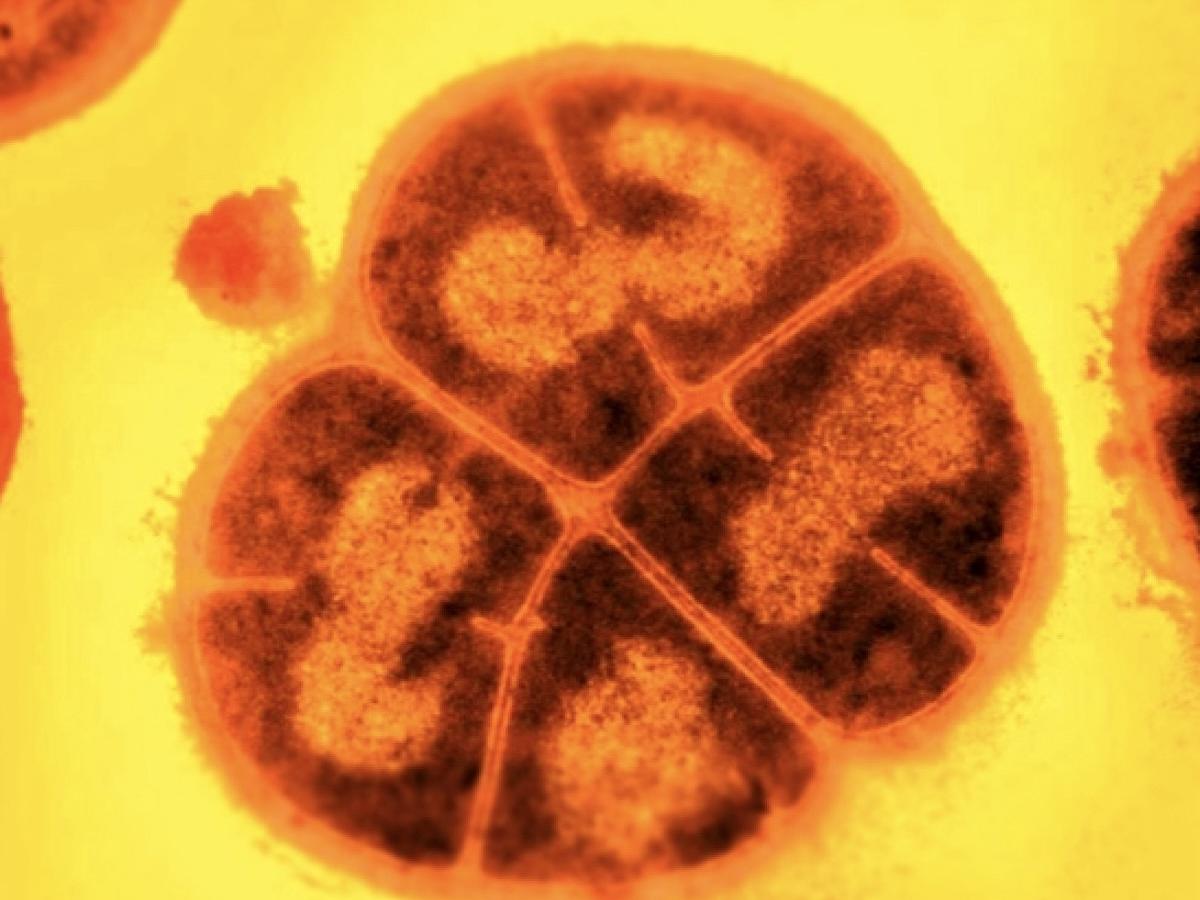

В России разработана новая тест-система, способная за 30-60 минут выявить опасную бактерию — синегнойную палочку, которая является частой причиной тяжёлых внутрибольничных инфекций. Это настоящая находка для медицины и не только!

Студенты Российского технологического университета (РТУ) МИРЭА разработали экспериментальную систему, основанную на использовании каталитических молекул ДНК. Эти молекулы, действуя как "молекулярные ножницы", узнают и расщепляют только специфические РНК-метки на определённых патогенах.

Синегнойная палочка — одна из самых опасных бактерий, поскольку устойчива ко многим антибиотикам. Её быстрое выявление критично, особенно для пациентов реанимаций и онкологических отделений.